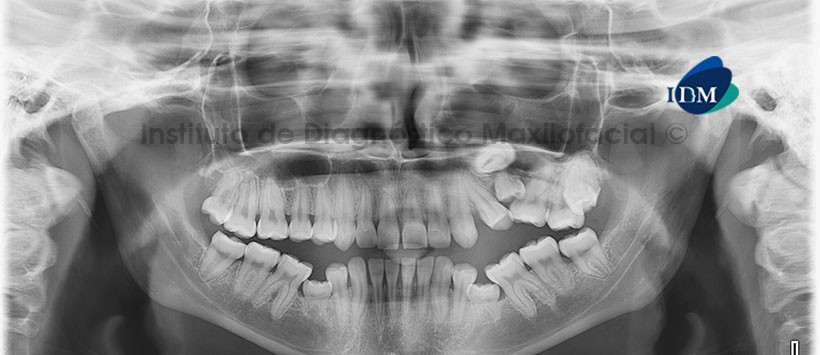

Paciente femenino, 18 años de edad, es referido al Instituto de Diagnóstico Maxilofacial (IDM) para descartar probable agenesia de premolares.

A la evaluación de la radiografía panorámica se aprecia persistencia de la pieza 6.5 que se encuentra en infraoclusión ocasionando la impactación de la pieza 2.5 y la divergencia radicular de las piezas 2.4 y 2.6. Así mismo se aprecia a las piezas 7.5 y 8.5 en persistencia y en infraoclusión asociados a la ausencia de los gérmenes dentarios de las piezas 3.5 y 4.5 (Figura 1)